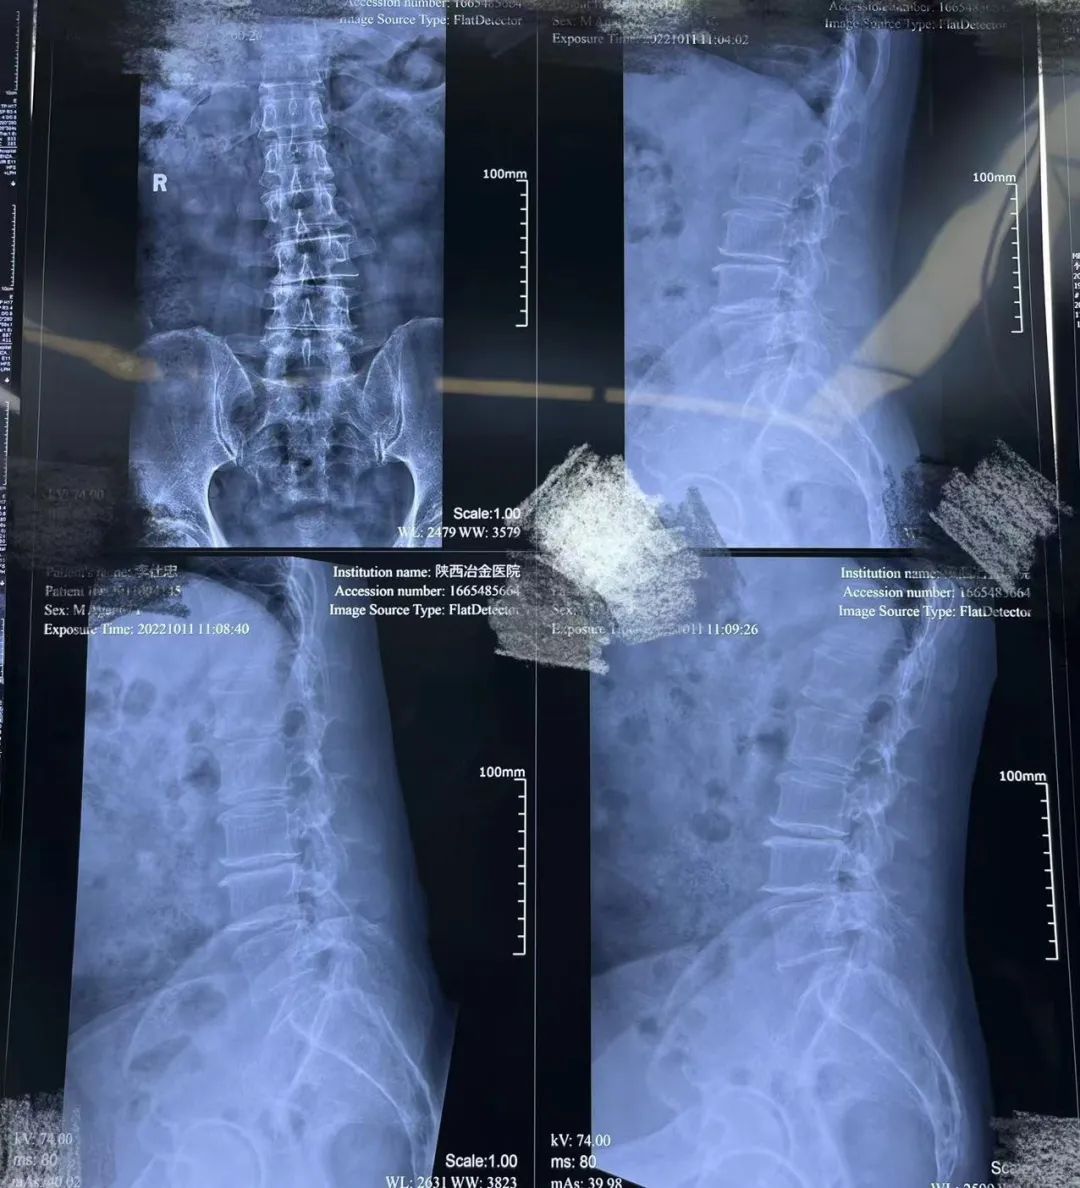

患者男,67岁,10年来腰痛缠身,休息后缓解,劳累后加重。近1年来腰部及右下肢疼痛、麻木不适。随着患者腰痛逐渐加重,经多方了解,家人陪同找到陕西冶金医院神经脊柱科就诊。入院后完善检查诊断为腰椎间盘突出、腰椎管狭窄。

▲术前X片